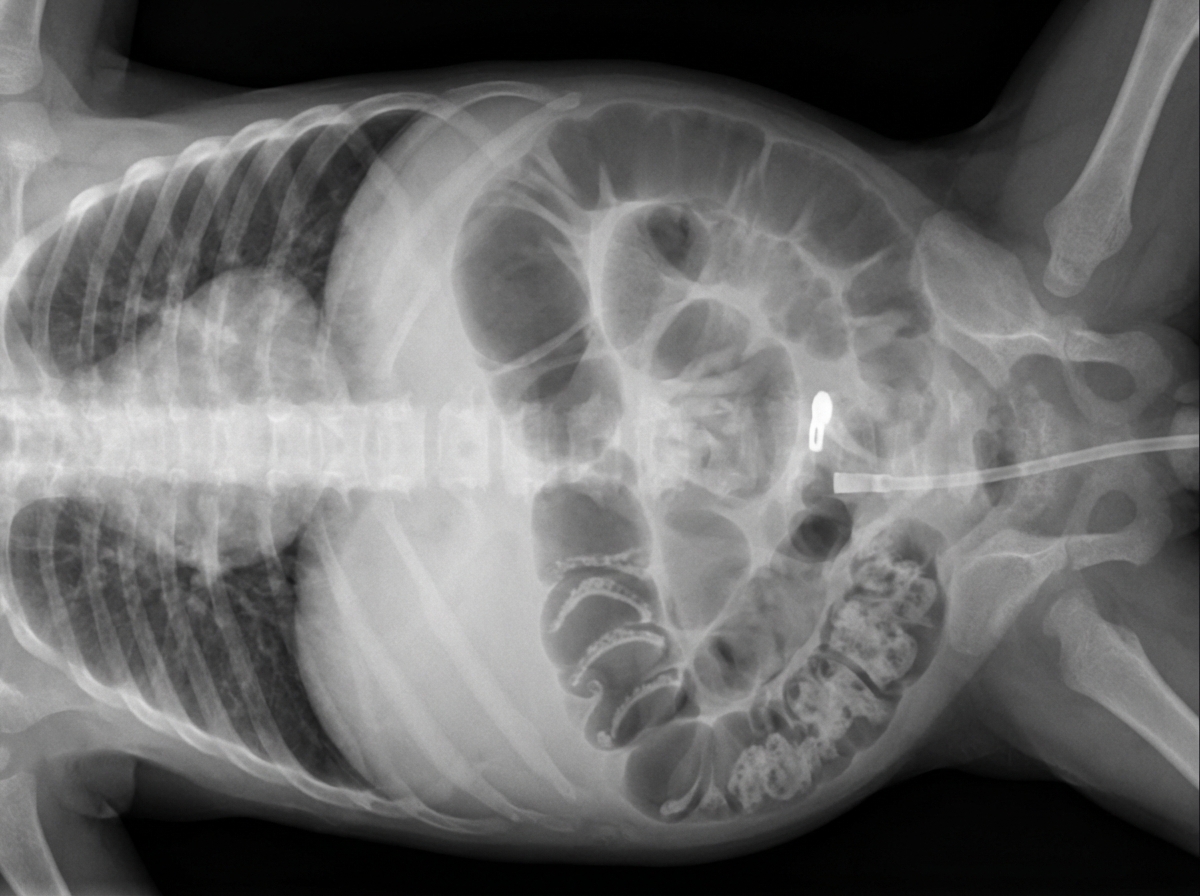

- Gas-producing organisms invade the bowel wall, causing the hallmark finding of pneumatosis intestinalis.

- Stage III (Advanced): Pneumoperitoneum (perforation).

⭐ Pneumoperitoneum on abdominal X-ray is an absolute indication for surgical exploration.

- Pneumoperitoneum on abdominal X-ray (pathognomonic for perforation).

⭐ Pneumoperitoneum on abdominal X-ray is an absolute indication for immediate surgical exploration in NEC. It signifies bowel perforation.

- Pneumoperitoneum on abdominal X-ray is the absolute indication for surgery, signifying perforation.